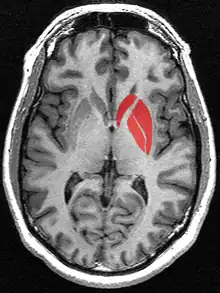

![]() Striatum shown in green with other basal ganglia and thalamus. Small region in yellow is the amygdala | |

![]() Tractography showing corticostriatal connections | |